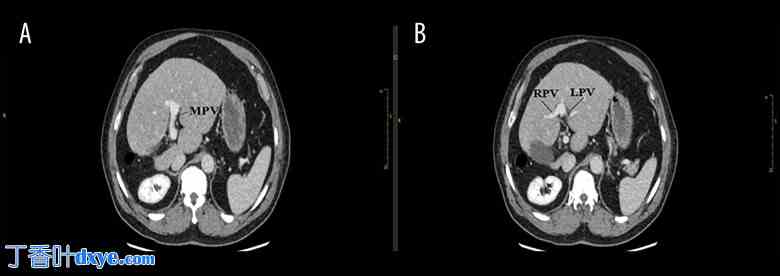

为排除任何异常,患者进行了腹部静脉造影CT检查。CT显示胆囊位于肝脏右背侧,胆囊颈部嵌顿有结石(图1)。肝右叶严重发育不全,左叶代偿性肥大。动脉视图可见肝右动脉起源于肝门,向下延伸,末端闭锁,可能通向萎缩的肝右叶(图2)。静脉视图可见肝右静脉(图3)。

图 1.

增强 CT 显示胆囊位置异常和肝右叶发育不良。AO – 主动脉;GB – 胆囊;K – 肾脏;Sp – 脾脏;St – 胃;L – 肝脏。箭头指示胆囊位于肝脏背侧。